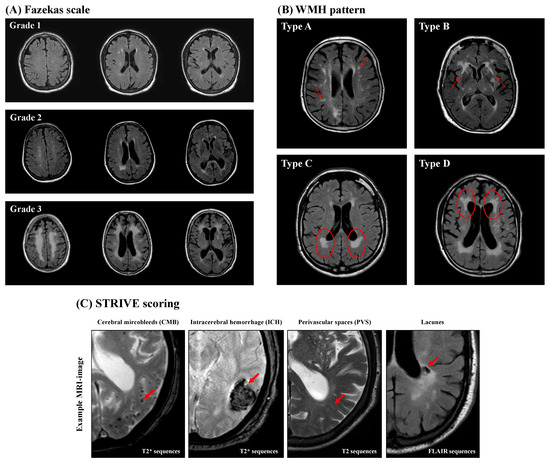

Background/Objectives: Intracranial aneurysms (IAs) may be connected to interactions between large and small intracranial vessels. We aimed to investigate the association between IAs and cerebral small-vessel disease (CSVD) and assess CSVD impact on IA patient management. Methods: This retrospective study analyzed [...] Read more.

Background/Objectives: Intracranial aneurysms (IAs) may be connected to interactions between large and small intracranial vessels. We aimed to investigate the association between IAs and cerebral small-vessel disease (CSVD) and assess CSVD impact on IA patient management. Methods: This retrospective study analyzed clinical data and MRI features of CSVD in 192 subarachnoid hemorrhage (SAH) patients: 136 with incidental IA, 147 with severe CSVD without SAH/IA, and 50 controls without SAH, IA, or severe CSVD. MRI assessments followed the Standards for Reporting Vascular Changes on Neuroimaging (STRIVE), with a total burden of small-vessel disease (TBSVD) score calculated. Statistical analyses included forward selection and binary logistic regression. Results: TBSVD differed significantly across groups (p < 0.001), except between SAH and IA groups (p = 0.8). Controls had the lowest TBSVD (1.00; 1.22 ± 0.996), followed by SAH (2.00; 2.08 ± 1.013) and IA groups (2.00; 2.04 ± 1.141), with the highest in the CSVD group (1.00; 1.22 ± 0.996). White-matter hyperintensity (WMH) patterns varied with IA rupture status (p = 0.044); type A was prevalent in SAH patients and type D in the IA group. Incorporating MRI CSVD features and TBSVD into risk assessments did not enhance IA prediction or outcome models. Conclusions: IA patients exhibit a higher CSVD burden than controls, suggesting a link between small and large intracranial vessels. WMH patterns distinguish between ruptured and unruptured IA patients, offering potential markers for IA rupture risk assessment and signaling a paradigm shift in understanding IAs and CSVD. Full article